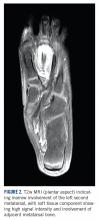

A 10-year-old girl visited our outpatient clinic with a painful progressive swelling on the dorsum of the left foot of 2 months’ duration. There was no history of antecedent trauma or fever. Physical examination revealed a bony hard swelling measuring around 5 x 6 cm on the dorsum of the left foot around the region of the second metatarsal. There was no regional lymphadenopathy or distal neurovascular deficit. She was evaluated with a plain radiograph that demonstrated a lytic lesion in the left second metatarsal associated with cortical destruction and periosteal reaction (Figure 1) . A subsequent magnetic resonance image (MRI) revealed a bony lesion destroying part of the left second metatarsal with cortical destruction and marrow involvement and affecting the soft tissue around the adjacent third metatarsal (Figure 2) . Needle biopsy showed chondroblastic osteosarcoma. Computed tomography (CT) of the thorax and bone scan were both negative for distant metastases.